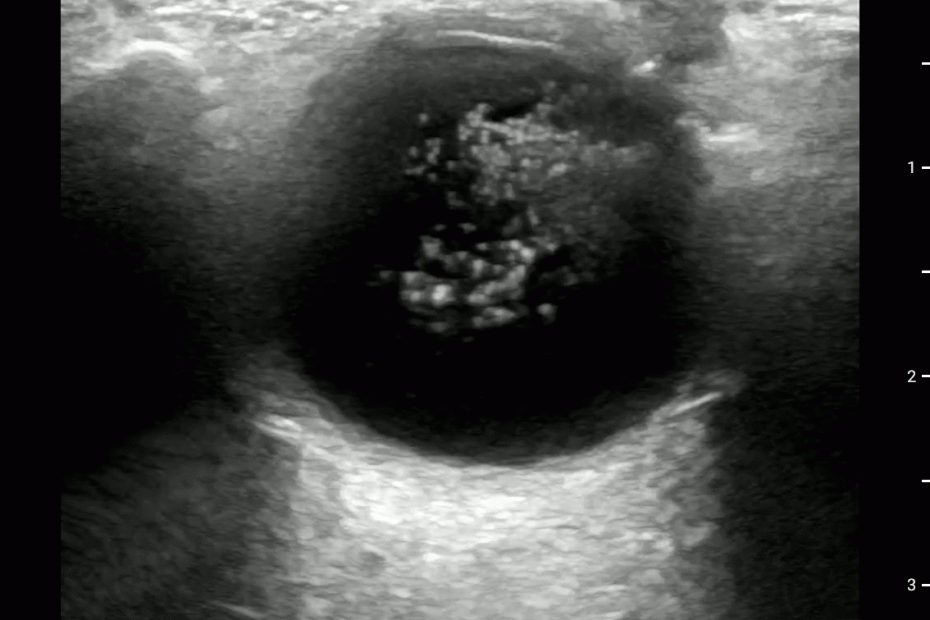

Asteroid Hyalosis